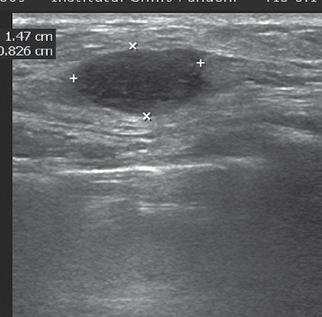

Limfomul mamar – o provocare diagnostic

Miruna-Elena Ispas, Prof. Univ. Dr. Ioana G. Lupescu, Șef

în evaluarea proceselor focale mamare